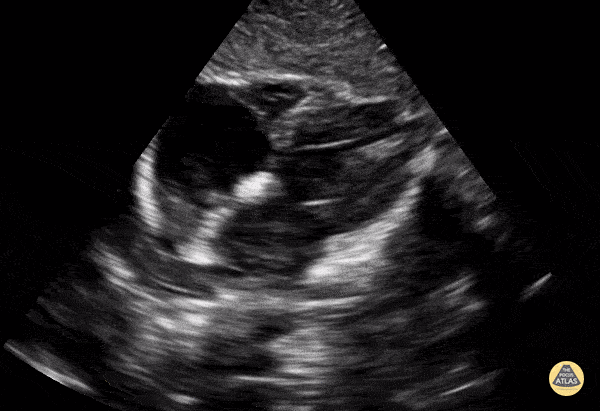

Normal subcostal view in a 9-year-old. Contributor: Jaron Smith, MD, Phoenix Children's Hospital

View: Unspecified Parasternal Long Axis Parasternal Short Axis Apical Four-Chamber Subcostal Four-Chamber Subcostal Inferior Vena Cava Right Upper Quadrant Left Upper Quadrant Suprapubic Longitudinal Suprapubic Transverse Subxiphoid Anterior Thoracic Phrenic